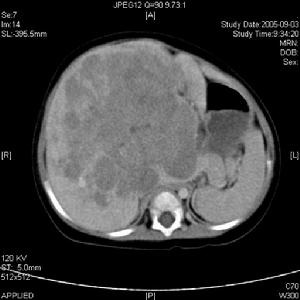

實體腫瘤的腎臟損害腫瘤導致腎損害相關的化驗異常有:

其它輔助檢查:

腎臟活檢:

1.光鏡檢查

(1)腎小球基底膜增厚呈膜型腎病。

(2)除腎小球基底膜增厚,尚有系膜增生,呈系膜毛細血管增生性腎炎

(3)單純系膜增生性病變。

(4)微小病變腎病。

(5)局灶節段性腎小球硬化。

2.免疫螢光檢查 免疫球蛋白IgG、IgAIgM和補體C3沿腎小球基底膜瀰漫性顆粒狀沉積,有時亦沉積於系膜區。

3電鏡檢查 於腎小球基底膜內、上皮細胞下、系膜區均可見電子緻密物沉積。